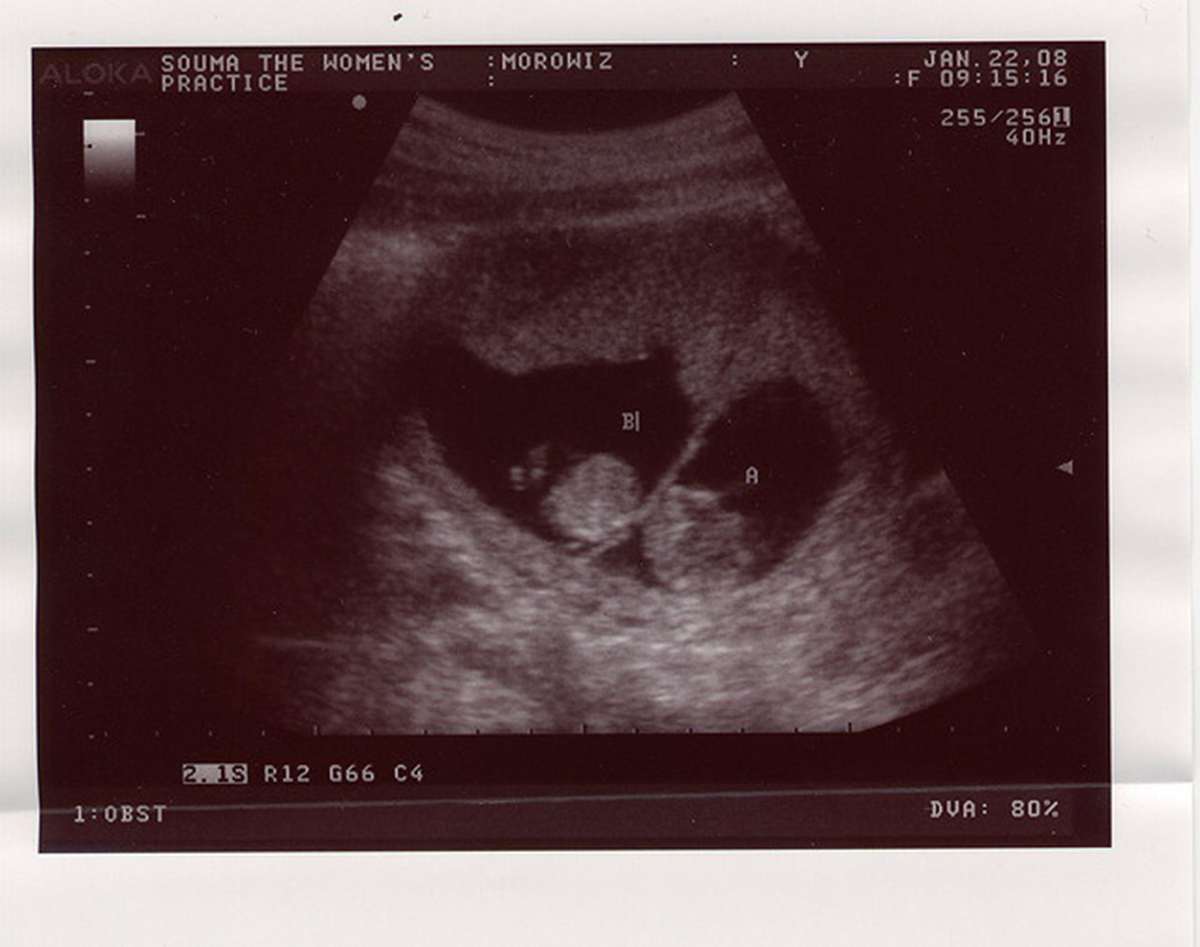

Selective reductions are usually carried out trans abdominally: using ultrasound technology, a potassium chloride injection is guided into the uterus and delivered to the selected fetus or fetuses. The injection stops the fetal heart. When done during the first trimester, the selected fetuses can be expected to be reabsorbed by the body, though some vaginal bleeding usually occurs.